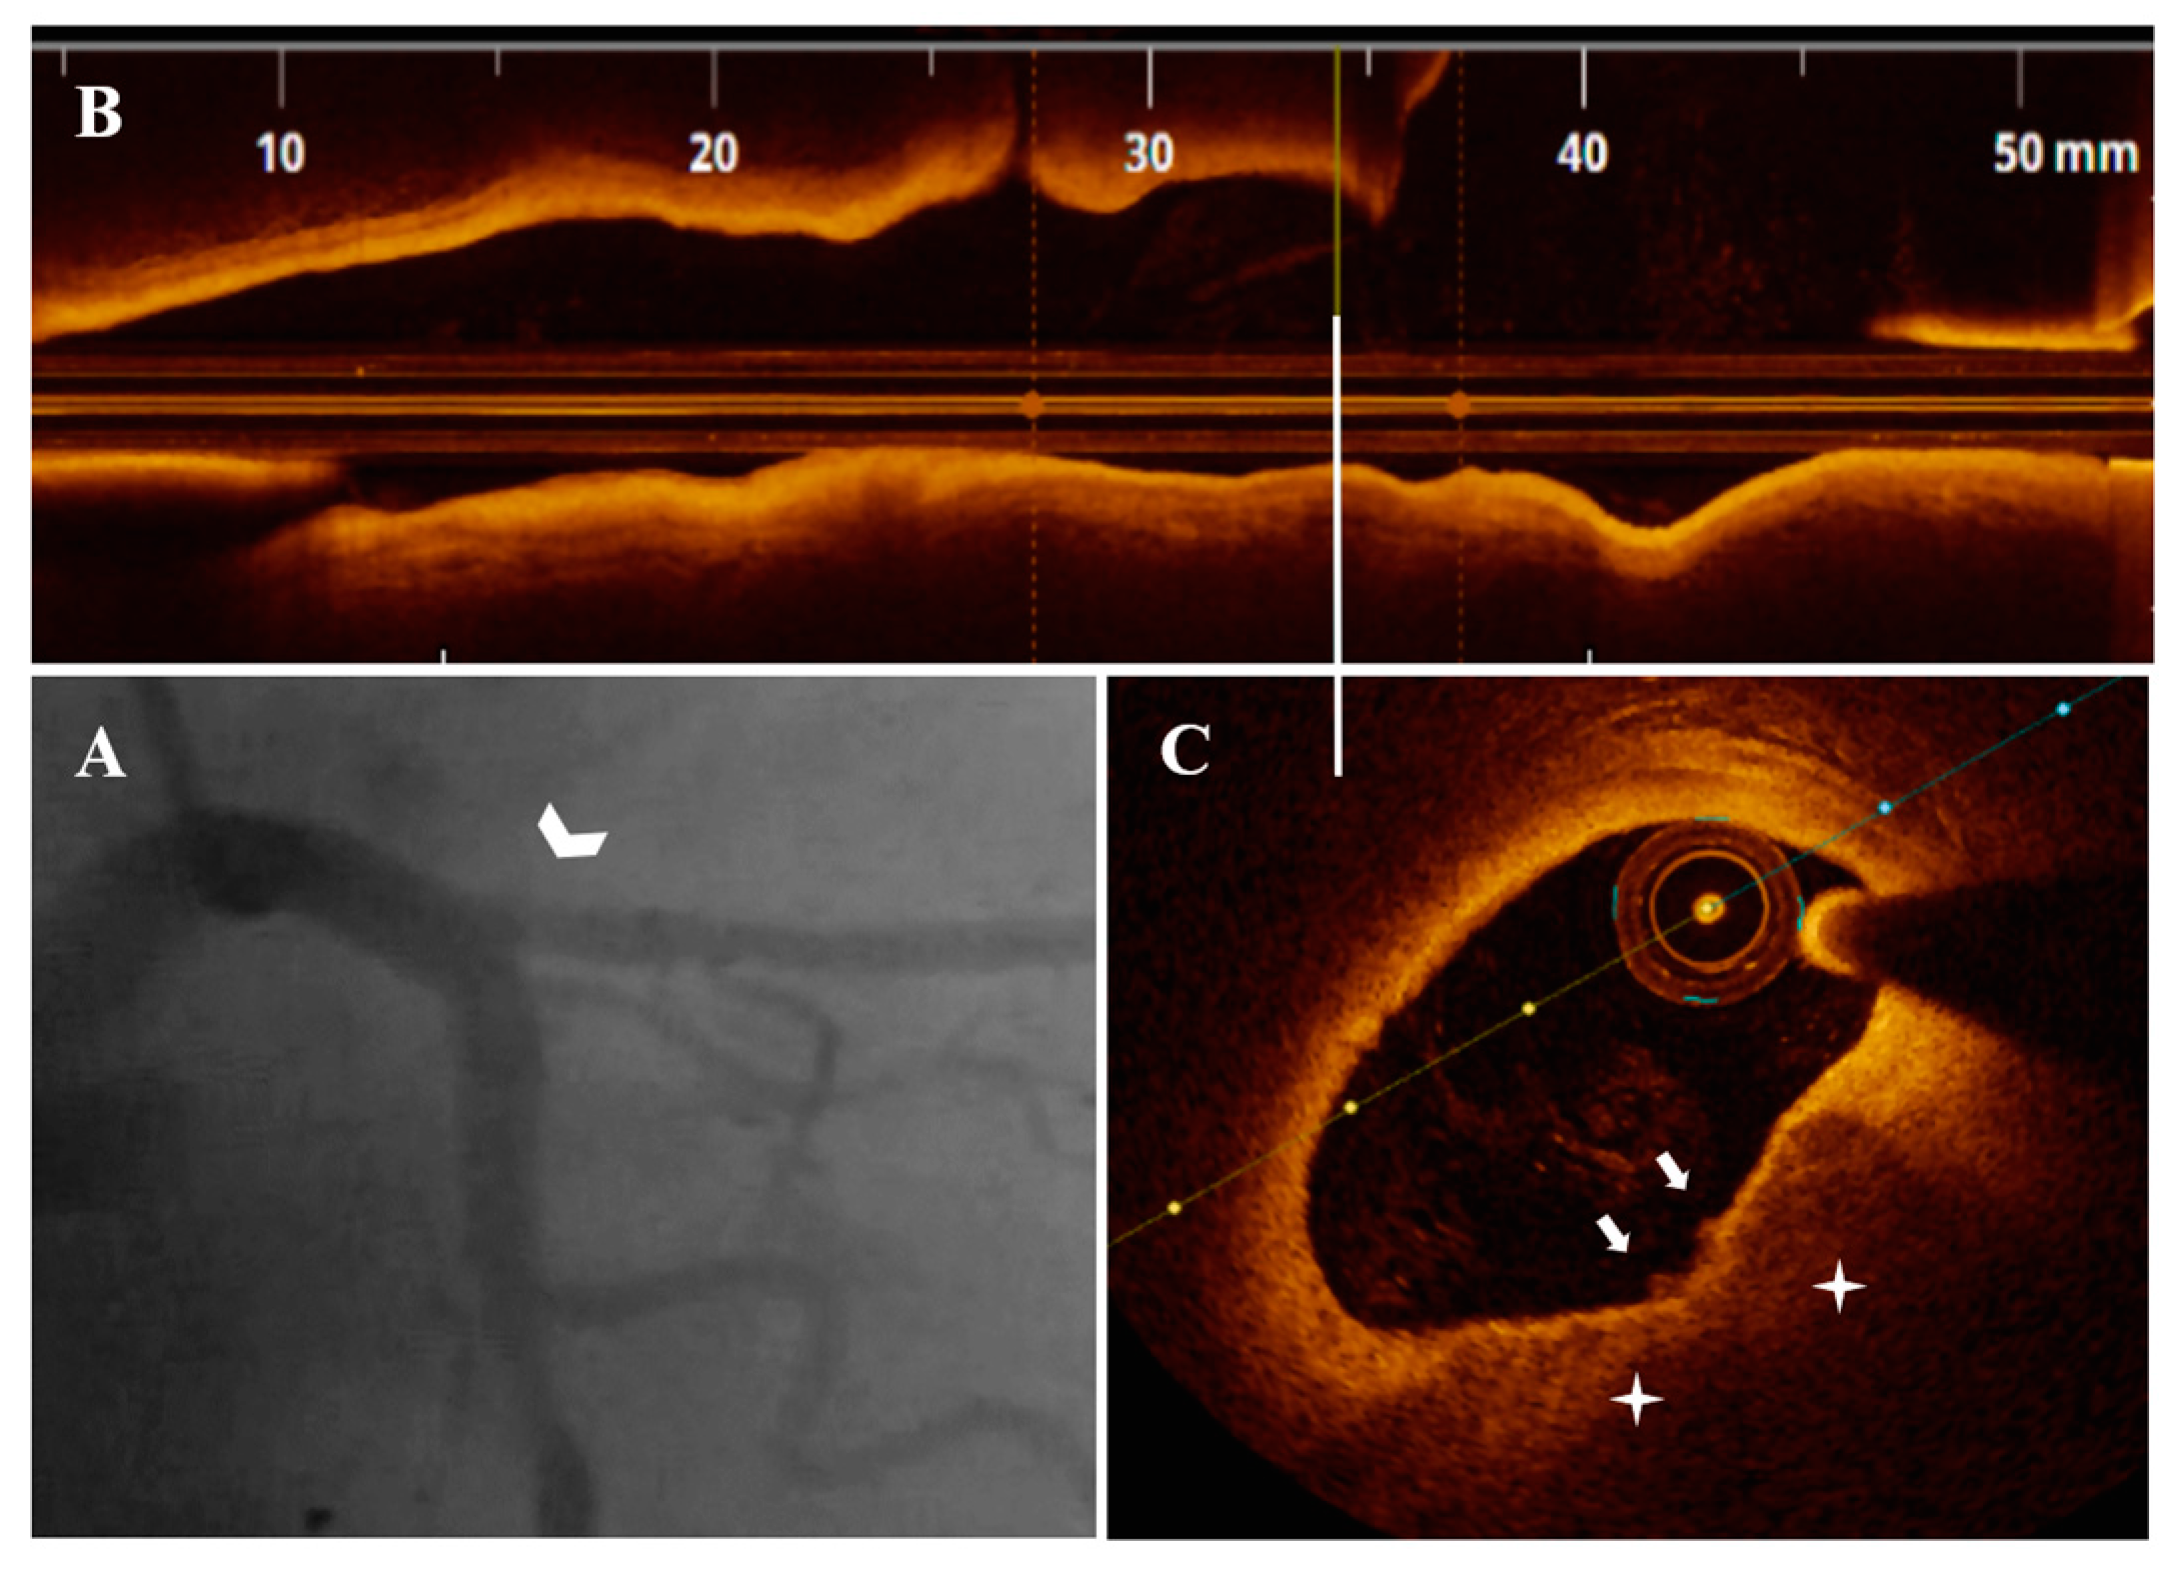

Figure 1.

A 74-year-old patient presenting with UAP. (A) CA—borderline proximal LAD (white arrowhead) and significant proximal second diagonal (blue arrowhead) stenoses. (B) OCT—LAD plaque longitudinal view. (a) Significant (area stenosis = 73.9%) stenosis after the origin of the second diagonal. (b–e) SCP (white star) presenting PE with white thrombi (white arrow) in the proximal plaque segment. (C) CA—final result after PCI with 2.75 mm DES/LAD and plain old balloon angioplasty/second diagonal.